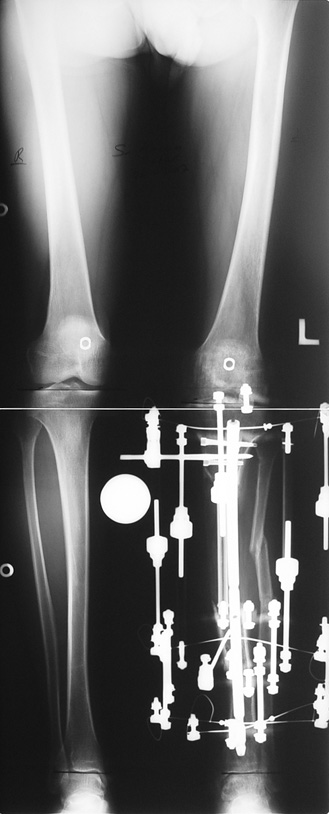

Appropriate radical debridement necessitates excision of all necrotic bone and soft tissues, and frequently causes instability at the involved extremity. The remaining bone and soft tissue defect has to be fixed and reconstructed. The distraction osteogenesis method of Ilizarov is used successfully for achievement of union, correction of the deformity, elimination of limb length inequality and reconstruction of segmental bone defects.

The duration of external fixation (external fixation index) depends on the amount of distraction required, and the extremity is prone to complications during this period. After the distraction phase is completed, the external fixator remains in place during the consolidation phase, which lasts twice as long as the distraction phase; but this period is hardly tolerated. If the external fixator is removed before sufficient consolidation is achieved, fractures, deformity and shortness will be the result. In our department, ‘lenghthening over nail’ method is used in order to decrease the external fixation index and increase patient comfort and activity level. In this method, the intramedullary nail is statically locked after the completion of the distraction phase, and external fixator is removed. The extremity is stabilized by the intramedullary nail during consolidation phase. In this way, complications due to long external fixation index or early removal of the external fixator are avoided.